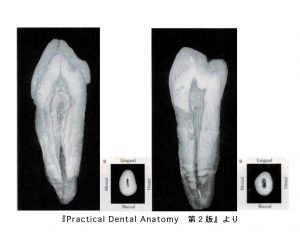

上下犬歯の中身

• 歯の外形を縮小した形で、細長い紡錘形を示す。

• 唇側面からみた根管は、歯頸側直下は少し幅広い。

• 隣接面からみると、唇舌径の大きな紡錘形を示し、歯頸側直下で唇舌的に幅広い。

上顎小臼歯の中身

• 歯の外形を縮小した形。頬舌面からみると棍棒状で、隣接面からみると髄室は幅広く、根管は細い。

• 2根管性が多く認められる。

• 第一小臼歯では完全分岐根管の他に、不完全分岐根管、網状根管が第二小臼歯よりも多く認められる。

• 根管は根尖側1/3で細く、根管の尖端は頬側および舌側に湾曲することが多い。